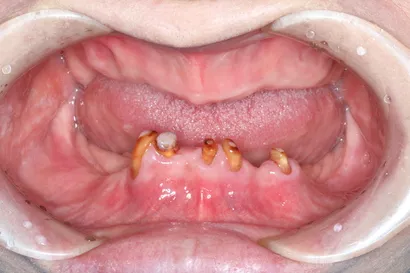

入れ歯からの全顎インプラント治療

50代 男性

執刀医 Dr.大杉 治療内容 重度の歯周病で、上下ともに顎の骨が大幅に痩せてしまった患者様です。総入れ歯も選択肢の一つでしたが、特に骨の吸収が激しい下顎では、安定せず「うまく噛めない・外れる」といった問題が予測されました。そのため下顎は、4本のインプラントで全ての歯を固定する「オールオン4」で、噛む機能を取り戻しました。

上顎:フルデンチャー(通常の粘膜を支えにした義歯)

下顎:ピンクポーセレンを用いたチタンフレーム入りのフルジルコニアインプラントブリッジ治療期間 1年3ヶ月 費用 上顎:75万 税抜

下顎:360万 税抜リスク 過去に歯周病と診断された方は、インプラントも歯周病(インプラント周囲炎)になるリスクが通常より高い傾向があります。そのため、治療後は特に注意が必要です。クリニックでの定期的なメンテナンスと、毎日の徹底したブラッシングを一緒に頑張り、インプラントを長持ちさせましょう。 -